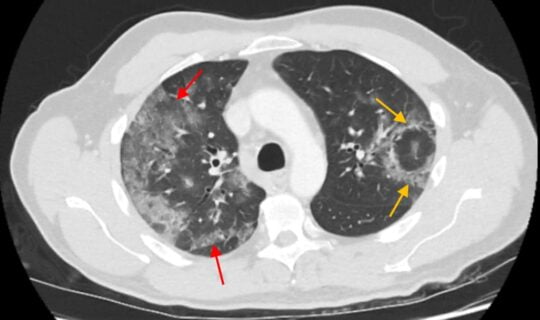

Coronavirus – What Radiologists Need to Know About the COVID-19 Pandemic!

Radiologists, learn essential COVID-19 imaging features and reporting guidelines to diagnose and manage pneumonia effectively.